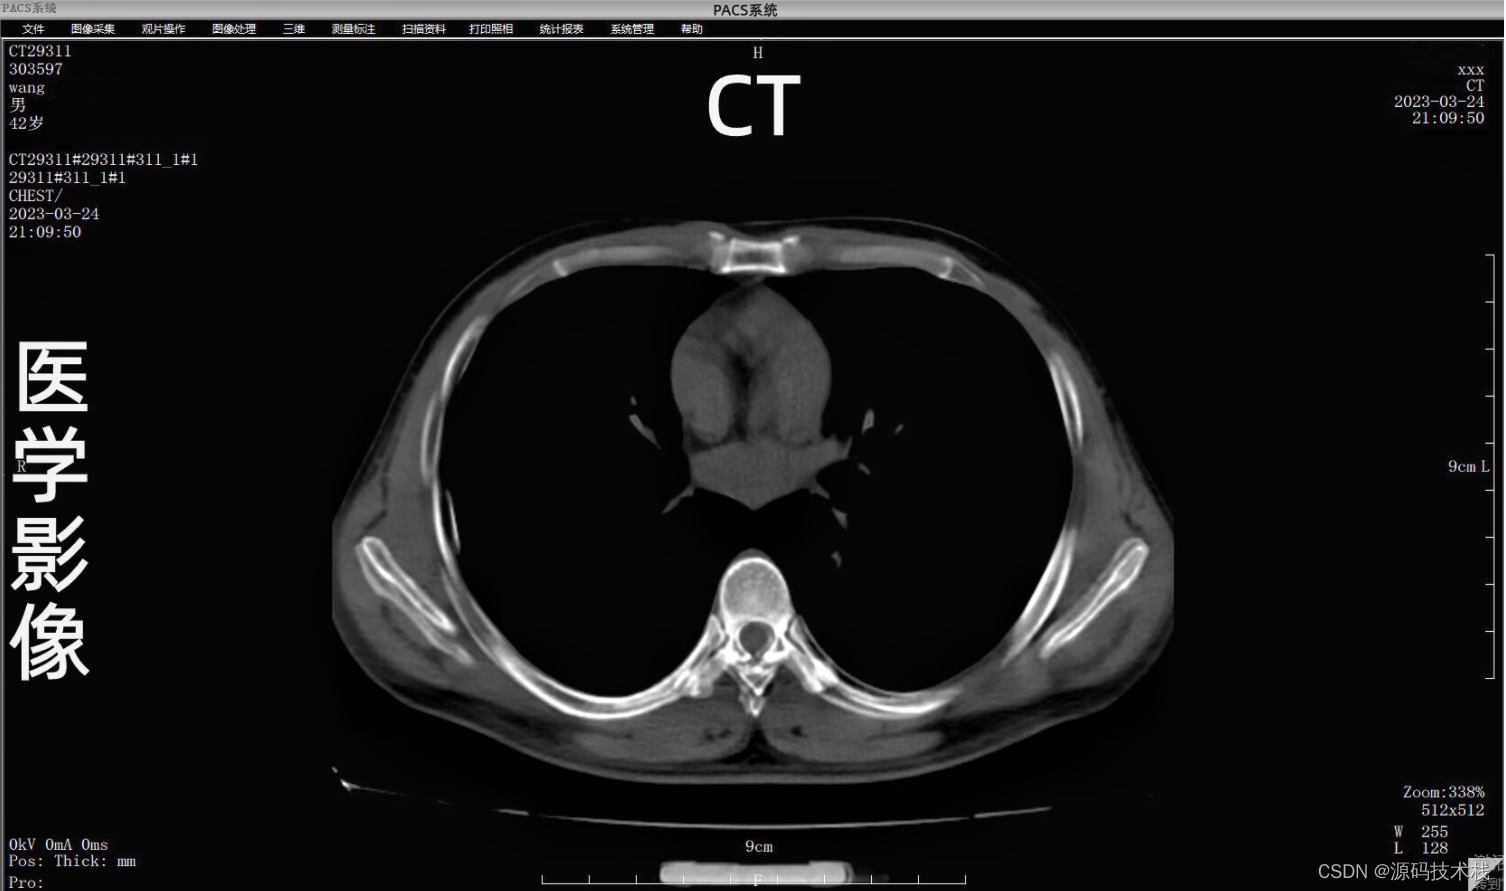

下面就是我们平时大家所做的CT平扫图像: